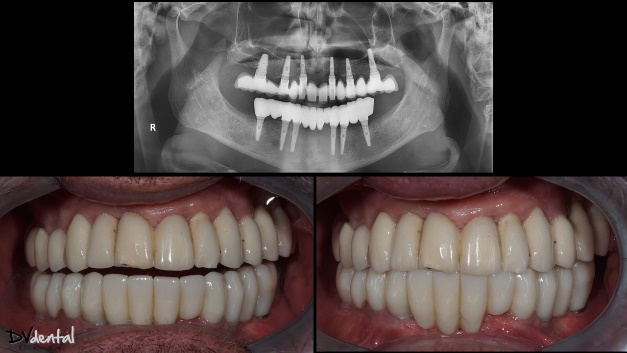

4. Примерка

Перед установкой постоянного протеза пациенту примерили прототип. Это хороший способ оценить эстетику и проверить плотность посадки, в том числе с помощью рентгена. После успешной примерки изготовили и установили постоянный протез (циркониевые коронки на титановой балке). Прицельная рентгенограмма показала, что он сел превосходно, и что внешний вид протеза получился ровно таким, как и планировалось. Пациент остался очень доволен результатом лечения.

Рис. 19,20: Напечатанный прототип протеза для примерки пациентом; проверяется пассивная посадка и прикус.

Рис. 21: Рентген показал хорошую пассивную посадку.

Рис. 22: Интраоральные снимки после лечения (слева: до лечения; справа: после лечения).